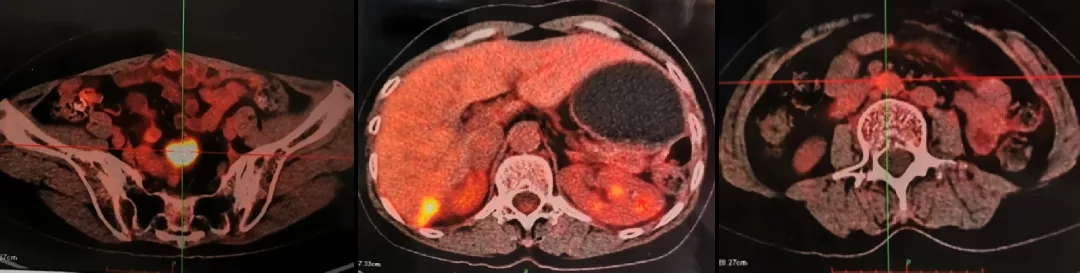

2013.5.6在我院(中国科学院大学附属肿瘤医院)检测CA125水平为298.8U/ml。CT:胸部(-),肝肾隐窝异常信号,脾脏前内方囊性占位灶,考虑转移灶;肠系膜上动脉水平、腹主动脉偏左侧结节灶;盆腔(-)。

2013.5.10 PET-CT:肝肾隐窝、脾肾间隙、脾门旁、腹膜后可见斑片状、囊实性及结节状影,实质部分FDG代谢增高,考虑转移。

2013.5.10 PET-CT检查结果